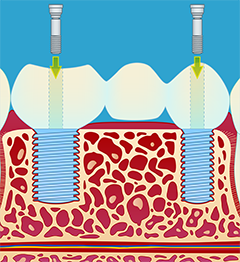

3.) Fremstilling og montering av kronen (fig III-V). Det er en tanntekniker som lager selve broen. Broen blir vanligvis festet med små skruer, slik at den senere kan tas av ved behov. Dette krever vanligvis 2 eller flere tannlegebesøk.

- En tannerstatning festet til implantater fungerer for de fleste pasienter som egne tenner, og den synlige delen av erstatningen ser ut som naturlige tenner. Et tannimplantat har likevel ikke samme form som en tannrot, og det kan det være vanskelig å gi overgangen mellom implantat og krone et naturlig utseende.